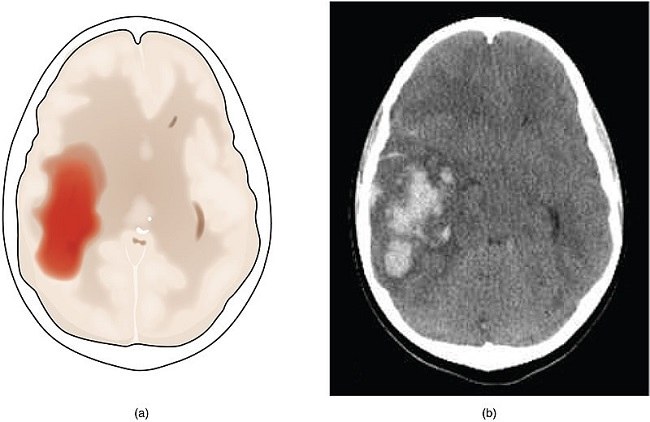

Pada kasus perdarahan intraserebral akut, pasien bisa mengalami ekspansi hematoma yang merupakan pertambahan volume hematoma >33% dalam 24 jam pertama. Hal ini meningkatkan risiko terjadinya cedera kepala primer dan sekunder.[1]

Ekspansi hematoma terjadi akibat pecahnya pembuluh darah yang berada di dekat perdarahan dari pembuluh darah yang pertama kali pecah. Faktor yang memengaruhi ekspansi hematoma adalah volume perdarahan intraserebral yang pertama, waktu kejadian dari ekspansi hematoma terhadap perdarahan intraserebral, dan penggunaan obat antikoagulan sebelumnya.[2]

Ekspansi hematoma sebagai komplikasi perdarahan intraserebral akut akan menambah mortalitas dan morbiditas. Mortalitas dilaporkan naik 5% setiap 10% kenaikan volume perdarahan intraserebral. Hal ini juga meningkatkan risiko sekuele neurologis.[2]